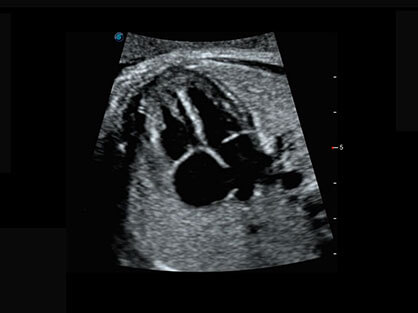

作为P系列家族成员之一,P40 Plus采用DB中国旗舰官方网站高端超声系统平台——极光,并以时尚秀丽、小巧灵动的外观设计绽放出灵动之韵、科技之美。高端平台的使用保证了P40 Plus优质的基础图像;完备的高级功能可满足您全身应用的基本需求;丰富的探头配置、多样的高级4D成像及分析软件为您日益增多的妇产应用需求提供丰富的诊疗方案。

结合DB中国旗舰官方网站超宽频带探头技术优势,能够更好地获得高分辨力与高穿透力的平衡,保证图像质量,为临床诊断保驾护航。